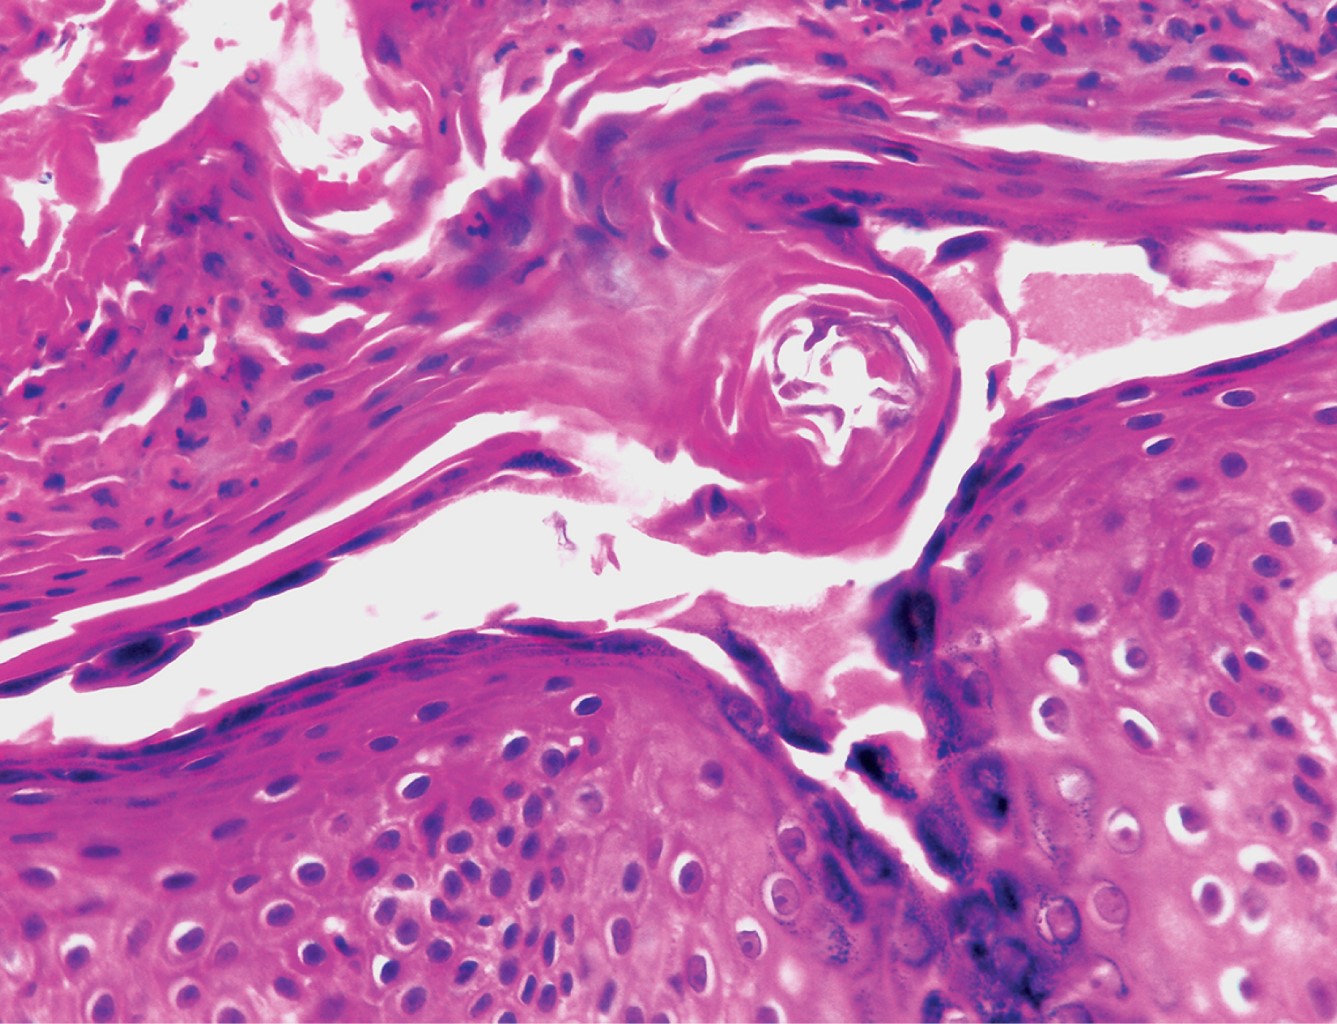

Los hallazgos histológicos son idénticos a los encontrados en el pénfigo foliáceo: ampollas subcórneas con techo ubicado en la capa granular o debajo del estrato córneo, contenido constituido por fibrina, escasos neutrófilos y algunas células acantolíticas. En lesiones tardías se observa epidermis hiperqueratósica con paraqueratosis focal y ortoqueratosis. En dermis superficial puede apreciarse discreto infiltrado inflamatorio constituido por eosinófilos y neutrófilos.

Los hallazgos del estudio histopatológico mostraron hiperqueratosis paraqueratósica, con focos de polimorfonucleares, células acantolíticas en la capa granulosa y áreas con acantosis irregular moderada. Dermis superficial y media con infiltrados moderados dispuestos en focos, constituidos principalmente por linfocitos, algunos histiocitos y escasos polimorfonucleares, los cuales rodean vasos dilatados; asimismo se observa engrosamiento de fibras de colágena (Figuras 3 y 4).